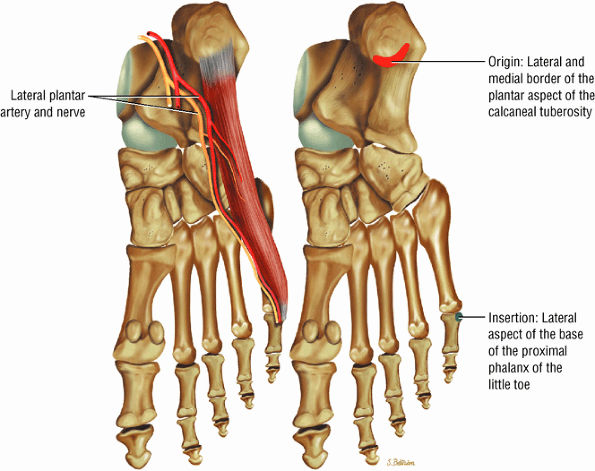

The muscles of the foot are the extensor digitorum brevis (Fig. 5.14), the abductor hallucis (Fig. 5.15), the flexor digitorum brevis (Fig. 5.16), the abductor digiti minimi (Fig. 5.17), the quadratus plantae (Fig. 5.18), the lumbricals (Fig. 5.19), the flexor hallucis brevis (Fig. 5.20), the adductor hallucis (Fig. 5.21), the flexor digiti minimi brevis (Fig. 5.22), the dorsal interossei (Fig. 5.23), and the plantar interossei muscles (Fig. 5.24).

FIGURE 5.17 ● ABDUCTOR DIGITI MINIMI The abductor digiti minimi inserts into the plantar plate and the lateral plantar aspect of the proximal phalanx of the fifth toe. The abductor digiti minimi abducts the fifth toe and assists in flexion.